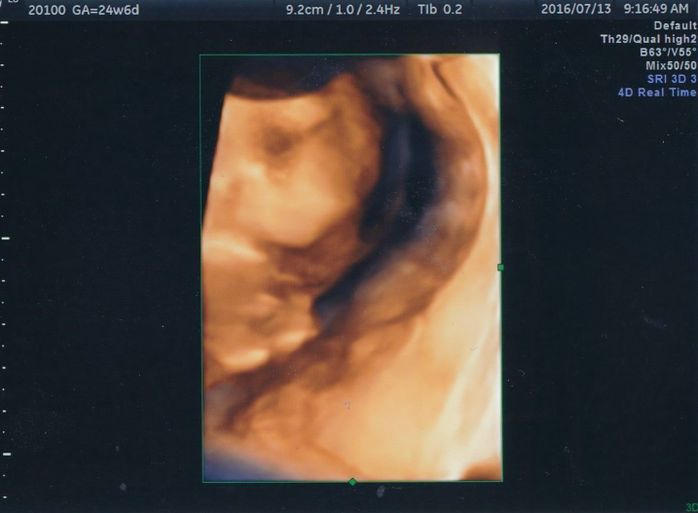

こちらは4D写真で、赤ちゃんの右向きの横顔です。おでこから鼻、口元までが写っています。この頃からどうやら女の子っぽいということを度々聞くようになり、私が以前2回目に経験していた妊娠は「きっと女の子だった」という思いから、私の中では「うんうん」と頷いていました。